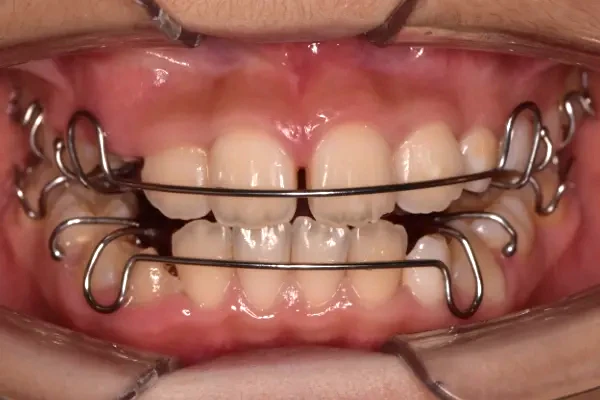

反対咬合

| 診断名・主訴 | 前歯反対咬合 |

|---|---|

| 年齢・性別 | 12歳・男性 |

| 治療期間・回数 | 1年半 18回 |

| 治療に用いた主な装置 | リンガルアーチ(前方誘導弾線) |

| 抜歯部位 | なし |

| 治療費 | 35万円(税抜) |

| リスク・副作用 | 装置による違和感・疼痛・歯肉退縮・歯根吸収・虫歯のリスクなど |

治療前

治療中

治療後